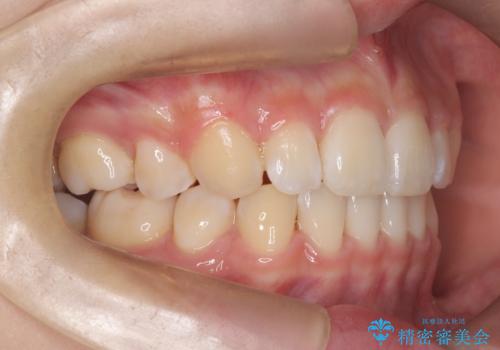

- ハーフリンガル

- 3年1ヶ月

- 出っ歯を治したいとのことで来院されました。

目立たない装置が希望とのことでハーフリンガルで治療をすることとしました。